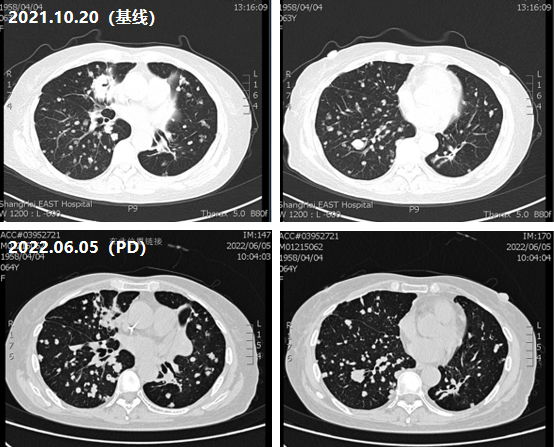

四线治疗(2021年10月——2022年6月)

治疗评估:鉴于患者使用含奥沙利铂化疗后再次PD,既往伊立替康化疗有效,建议患者再次使用伊立替康;

治疗方案:贝伐珠单抗联合FOLFORI方案;

疗效评估:2022年6月5日,患者肺部病灶再次出现增多,提示PD;

图4 四线治疗CT影像评估